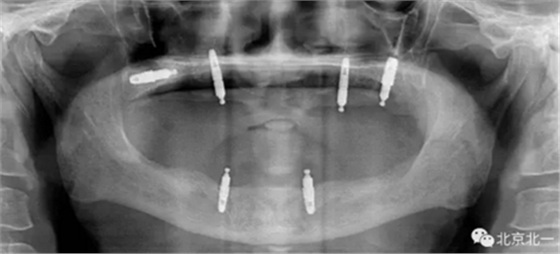

圖五:北一種植王明老師出馬,采用外側(cè)壁開窗微創(chuàng)取出術(shù)。

圖六:術(shù)中看見了植體

總結(jié):植體脫落得原因很多,最常見的因素有感染或者污染,植體自動松動,沒有骨結(jié)合,過早負重,導致植體在沒有完全骨結(jié)合后受力過大脫離, 或者植體在常規(guī)負重后一年內(nèi)脫落,可能因為咬合設計不合理,或者種植體維護不到位等因素,病人自身因素也是一個不可忽視的因素,某些系統(tǒng)性疾病等。